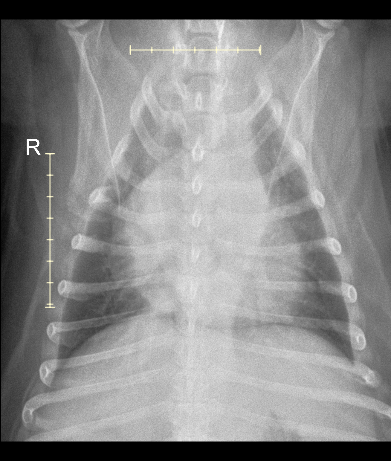

After checking in Gavin and I took a stroll outside, and were called in a few moments later. He and I were taken to a nearby exam room by a technician, and greeted by an oncology team member. After an initial intake and questionnaire, their team took Gavin in the back for a quick check of his mouth, leaving me and my thoughts alone in the room… After ten minutes, their team comes back noting that they’re 99% positive the growth is cancer, possibly melanoma, and that such may have already spread from his mouth to orbital bone / eye socket, and that it may be present in his lungs. At this point my only goal is to obtain information; happy to pay whatever cost for the sedation, needle biopsy, and radiology recommendations.

I leave Gavin in their carefully trained hands. Two hours later I receive a call from their reception team gleefully saying Gavin is awake, and that I may come back to pick him up and chat with the team to discuss their findings. Long story short - cancer is a fibrosarcoma, lungs are clear, and that they expect Gavin to live another three to six months depending on how the tumor continues to grow.